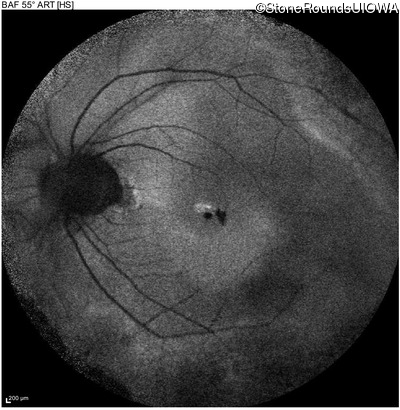

Blue Autofluorescence - Right - 20/25 sc

Exemplar